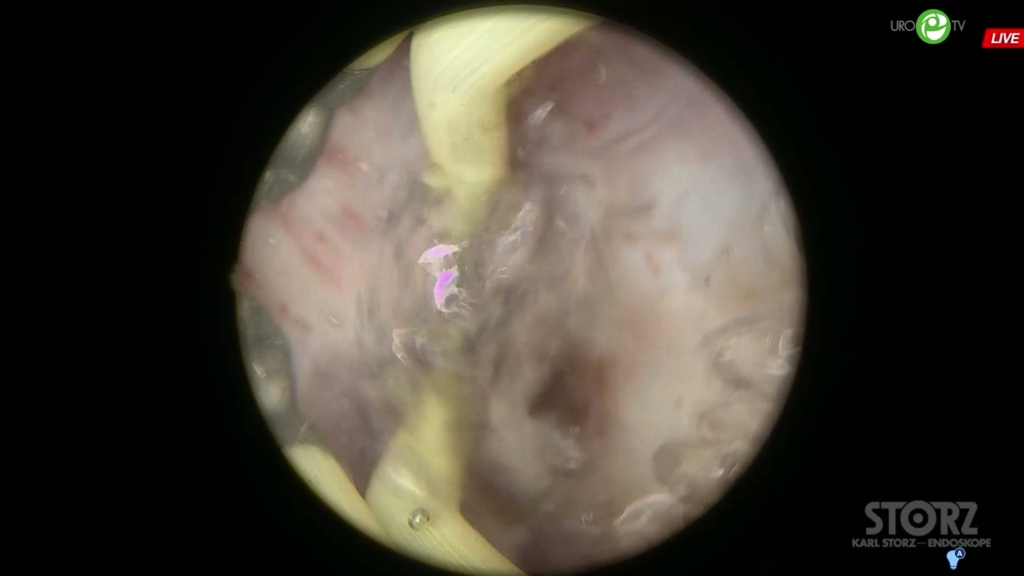

Холтобин Д.П. - Биполярная ТУЭП

ДГПЖ